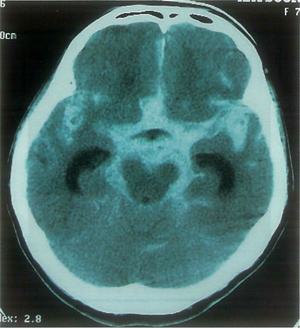

58歳の男性。右利き。職場で倒れているところを発見され搬入された。意識は傾眠状態であったが、発症後4日で改善した。この時点での発話には異常がない。左手足に重度の運動障害と感覚障害とを認める。筋緊張は低下している。視力・視野は正常であるが、顔面は常に右方に向け、指摘しても左側を見ようとしない。頭部CTを示す。この患者に該当すると考えられるのはどれか。

1

①

2

②

3

③

4

④

5

⑤